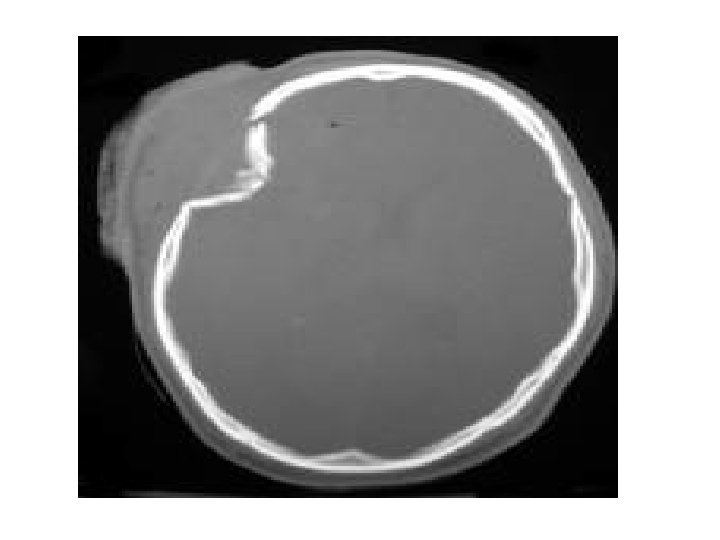

Depressed fracture